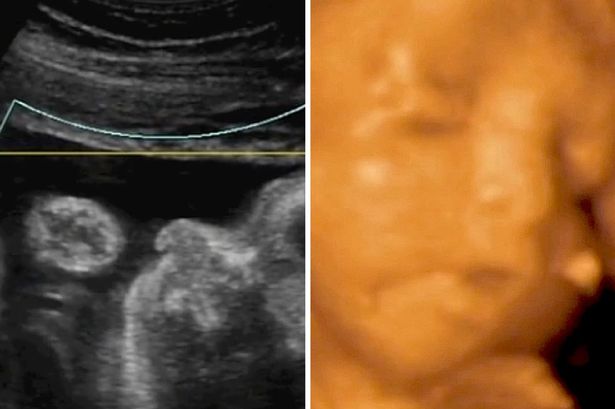

Mit csinál a baba a méhben? Döbbenetes felvétel: eszik, sír, tüsszög a magzat!

Alexandre Lambert és férje amikor látták a fiúgyermeket 4D-s ultrahang vizsgálaton keresztül, teljesen megdöbbentek

“Az első dolog, amit mondtam a feleségemnek:” Wow! Úgy néz ki, mint a bátyád!”